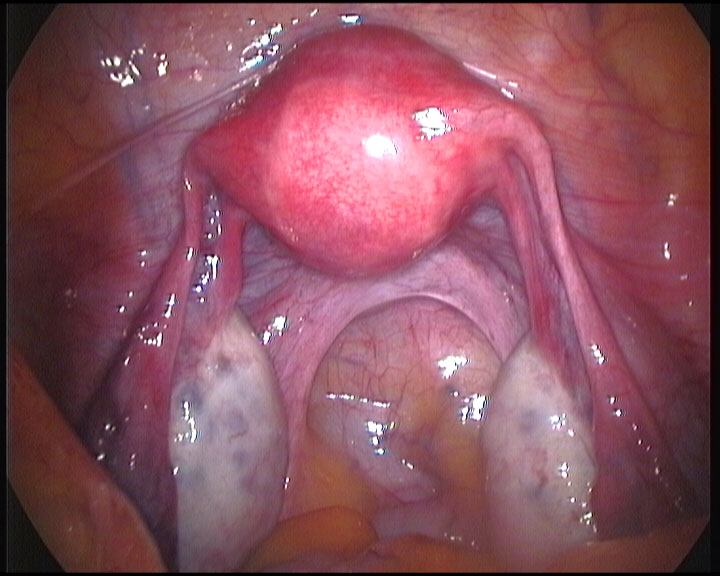

Hystero Laproscopy (हिस्टेरोलॅप्रोस्कोपी)

P.C.O Drilliing (दुर्बिणीच्या शशस्त्रक्रियेद्वारे अंडाशयावरची सूज कमी करणे)